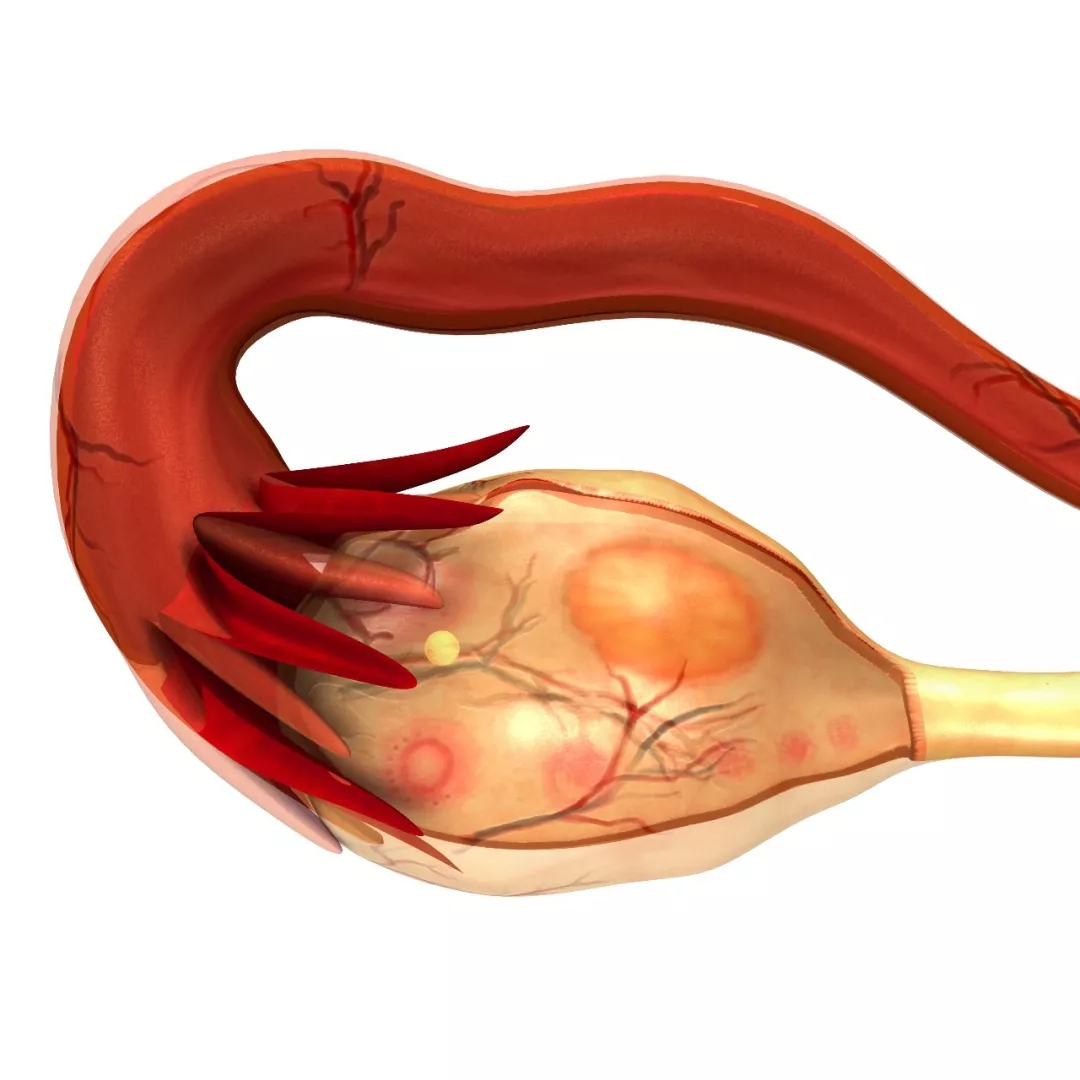

Q13 卵巢早衰也会对女性备孕和生育产生影响吗?

是的,卵巢早衰是遗传因素和环境因素导致的,还有精神的高度紧张、劳累等其他因素,从而导致一系列的内分泌和生殖方面的问题。

如果从临床上自身感觉来看,第一个表现就是月经紊乱,它会出现月经稀发、闭经,有些人还会出现围绝经期的表现,比如说盗汗、烦躁、易怒、面部皮肤衰老、生殖器官干涩等。

按照国际界定的标准,一般是在40岁之前,如果出现了上述的症状,就应该就医了。

目前来说,对于卵巢早衰和卵巢功能不全的问题我们没有什么特效的办法,最重要的保养方法还是早期发现,如果能够尽早地发现易感因素并去除,避免一些会导致卵巢早衰的风险因素。

另外,如果出现了症状及时就医,医生会给予一些药物进行调整,可以更早干预、更早帮助女性的卵巢功能。比如,当出现卵巢功能不全的时候,我们会用激素替代治疗;当患者的月经出现紊乱、情绪出现波动的时候,应及时找生殖医生排除一下是否是卵巢方面的问题。